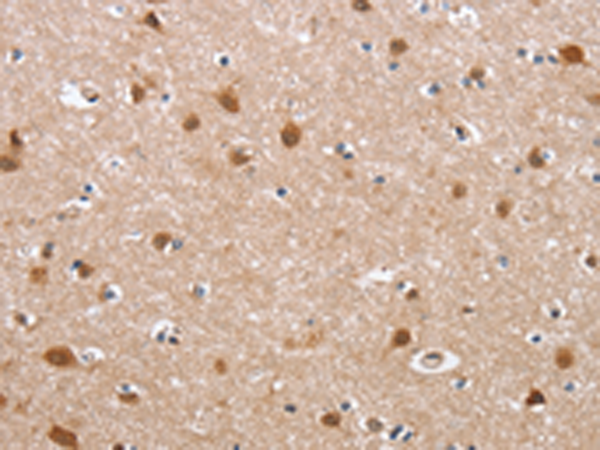

IHC positive control: |

Human brain |

IHC Recommend dilution: |

50-200 |